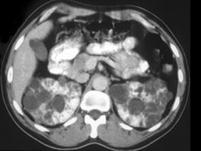

女,35岁,请根据CT图像,选择最可能作出诊断 ( )A、多囊肾B、单纯性肾囊肿C、多发性肾囊肿D、肾脓肿E、囊性肾癌

问题 女,35岁,请根据CT图像,选择最可能作出诊断 ( )

选项 A、多囊肾 B、单纯性肾囊肿 C、多发性肾囊肿 D、肾脓肿 E、囊性肾癌

答案 A